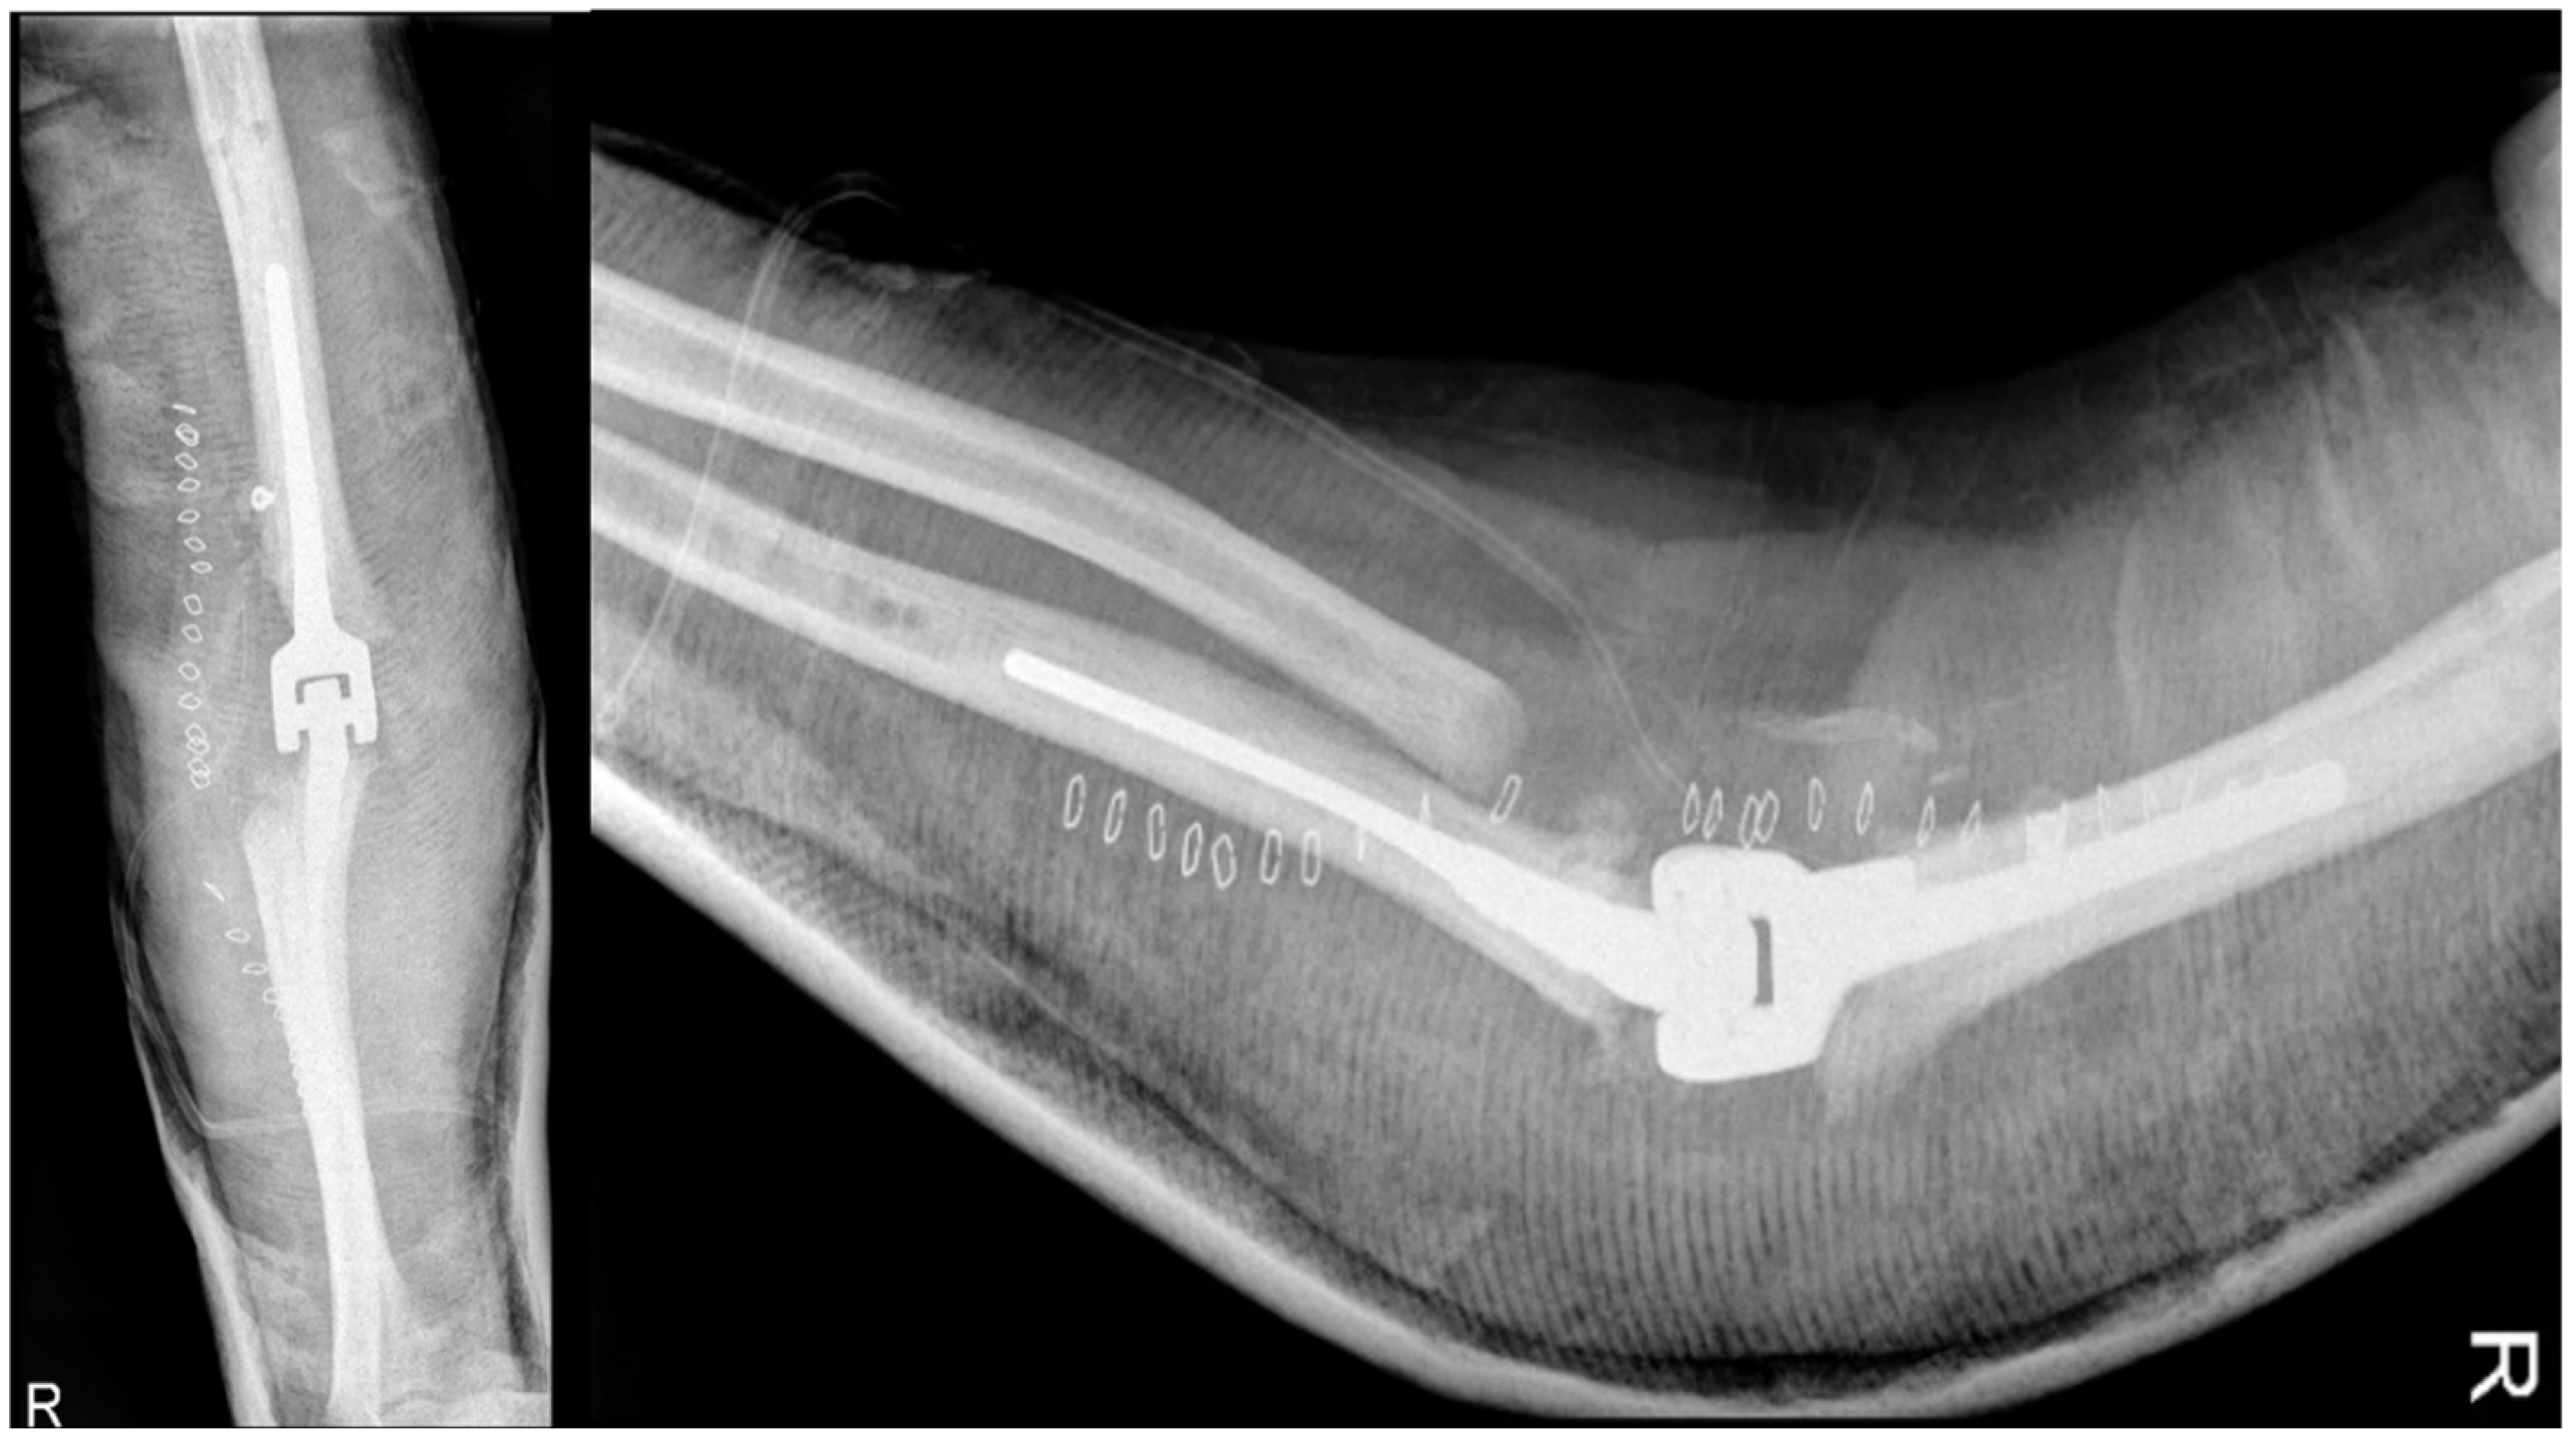

The patient in question underwent an open debridement with synovectomy and arthroscopy in April 2012 to address the advanced stage of hemophilic elbow arthropathy. During the procedure, the surgeon observed bone resorption with free fragments in the joint, primarily in the radial head, and a thickened capsule with evidence of synovitis. The dislocation was structured and non-reducible. Samples of bone and synovium were collected and cultured for pathogenic microorganisms, which returned positive results for different types of coagulase-negative Staphylococcus. Postoperative radiography revealed the removal of some fragments at the joint level, but the elbow joint dislocation persisted as shown in Figure 5. Synovium fragments showed fibrosis, calcification, scattered foci of chronic inflammation, synovial hyperplasia, and abundant superficial fibrin stores. The bone samples displayed trabecular remodeling and peritrabecular fibrosis with spared perivascular reactive lymphoid aggregates.

Figure 5.

Post-synovectomy and debridement surgery, anteroposterior and lateral views of the right elbow. Reduction in the periarticular mass but persistent joint dislocation.

In August of 2013, a surgical operation was conducted to fuse the elbow joint using a plate with twelve holes and a ninety-degree flexion angle, utilizing the same surgical access point as the previous operation (as depicted in Figure 6). During the course of the procedure, the anatomical structures of the ulna, radial head, and distal humerus were significantly distorted and unidentifiable. New synovectomy and osteotomy were carried out to apply the plate. Following the patient’s release from the hospital, they were instructed to wear a brace at a ninety-degree angle and an arm sling, undergo physiotherapy to move the fingers and wrist, and undergo an X-ray examination thirty days post-surgery.

Figure 6.

Post-arthrodesis X-ray anteroposterior and lateral views of the right elbow. (a) Post operative images showing the plate in site. (b) Thirty days after images with mobilization of the synthesis with broken screws.

Arthrodesis and Complications

At the 30-day postoperative follow-up, radiography revealed three broken screws in the proximal humeral shaft and a subtle periosteal reaction around the plate. The patient was referred for fixation revision and was protected with a new brace. The screws and plates were removed using the previous lateral elbow access. However, internal fixation was not feasible due to the resemblance of the last 7–8 cm of the distal humerus to a cortical lamina. Consequently, an external fixator, bar-to-bar, was applied after the arthrodesis surfaces were prepared. as shown in Figure 7, the follow-up radiograph confirmed the appropriate positioning of the device. At hospital discharge, the orthopedic recommendation was to wear the external fixator for 60 days, rest, and undergo weekly ambulatory assessments of local clinical findings.

Figure 7.

X-ray anteroposterior and lateral views of the right elbow after the External Fixator positioning to stabilize the elbow joint.